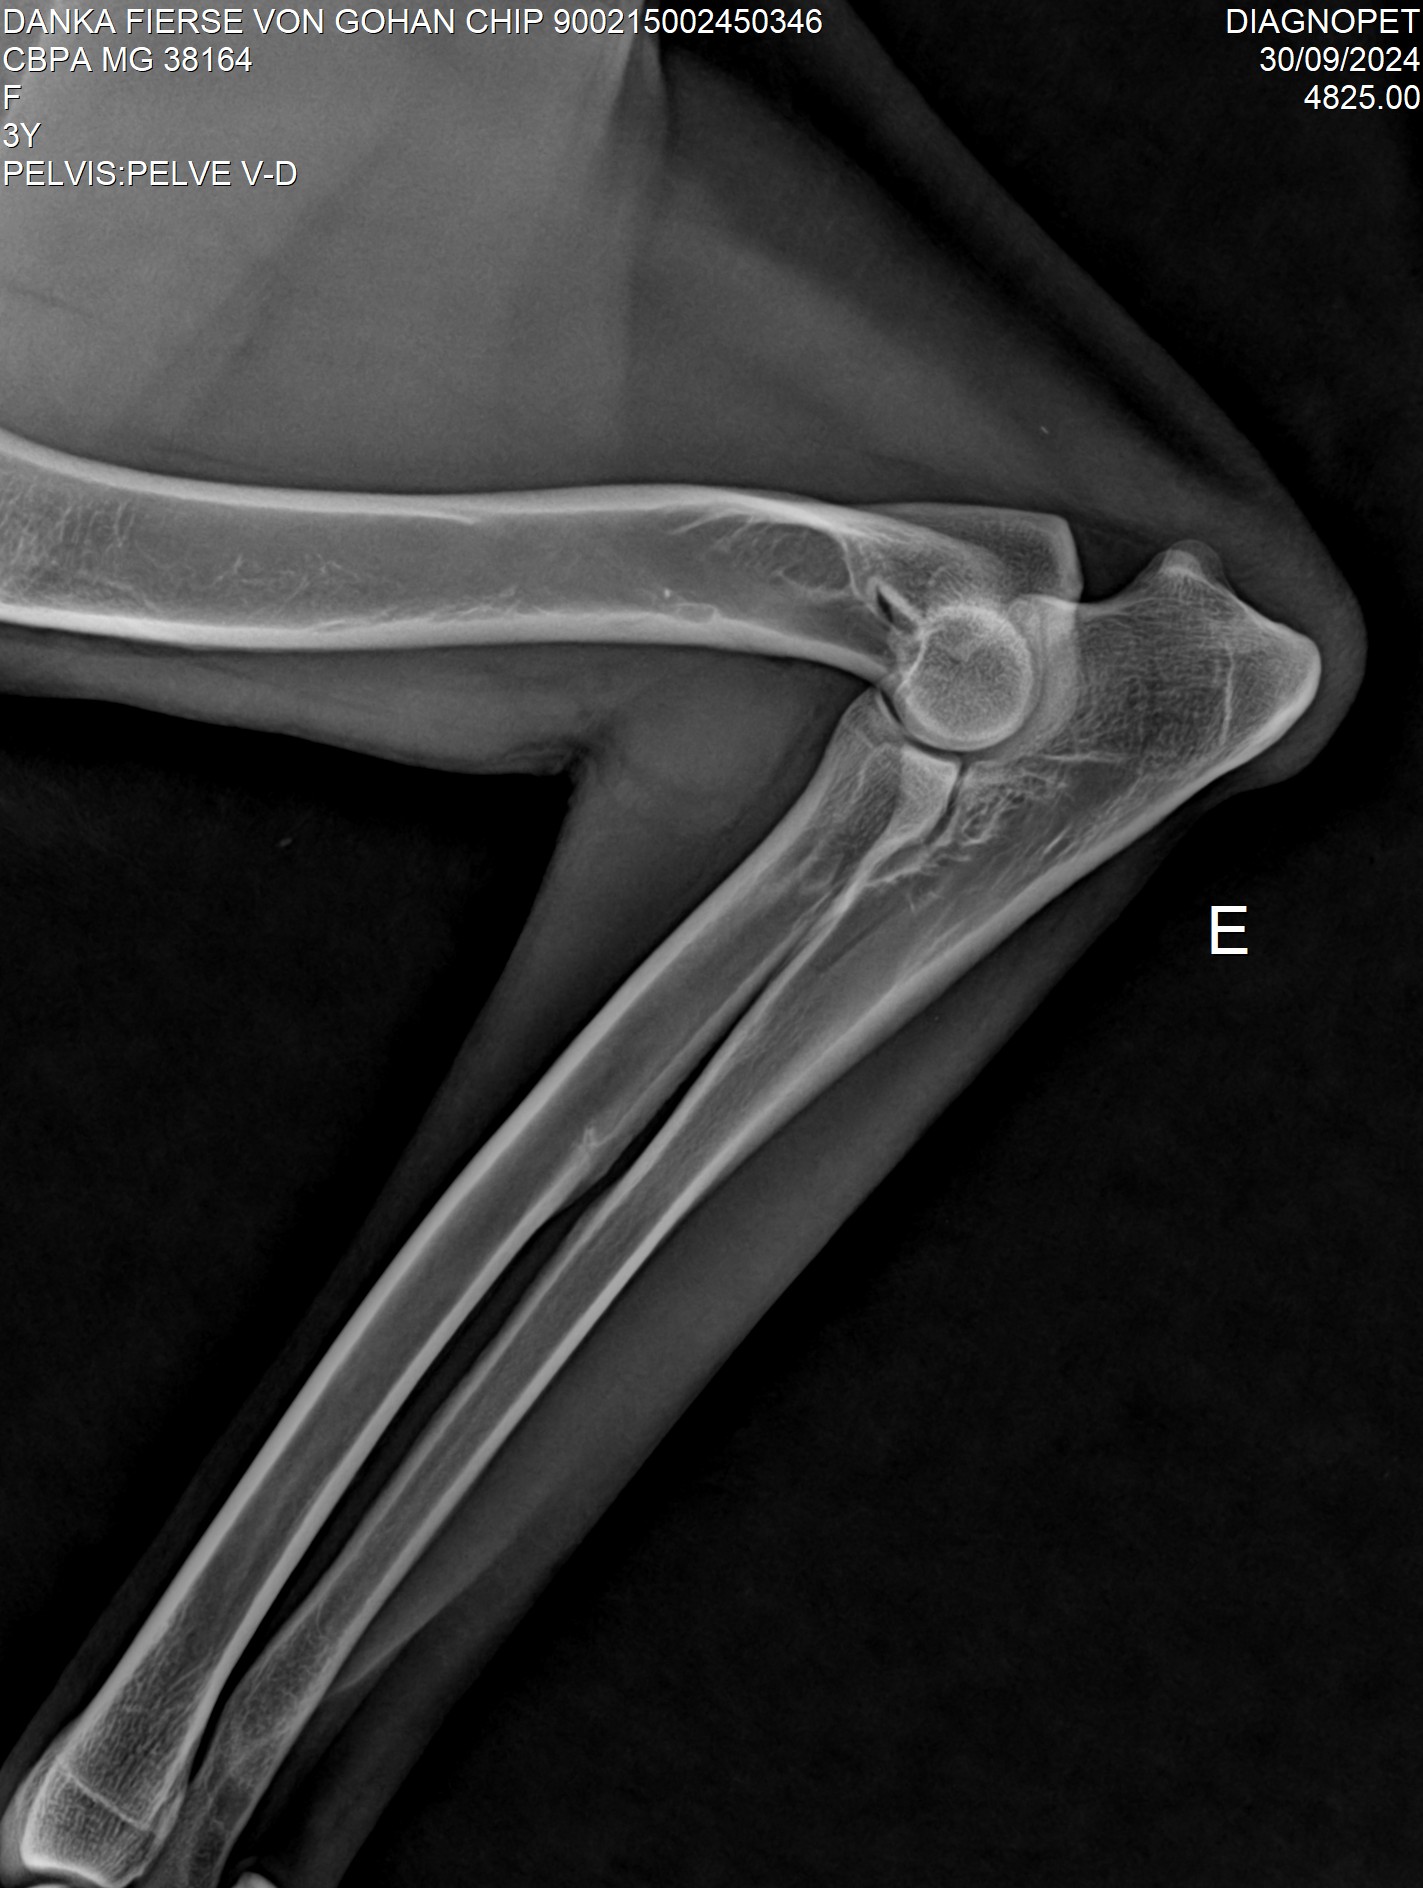

Raio X